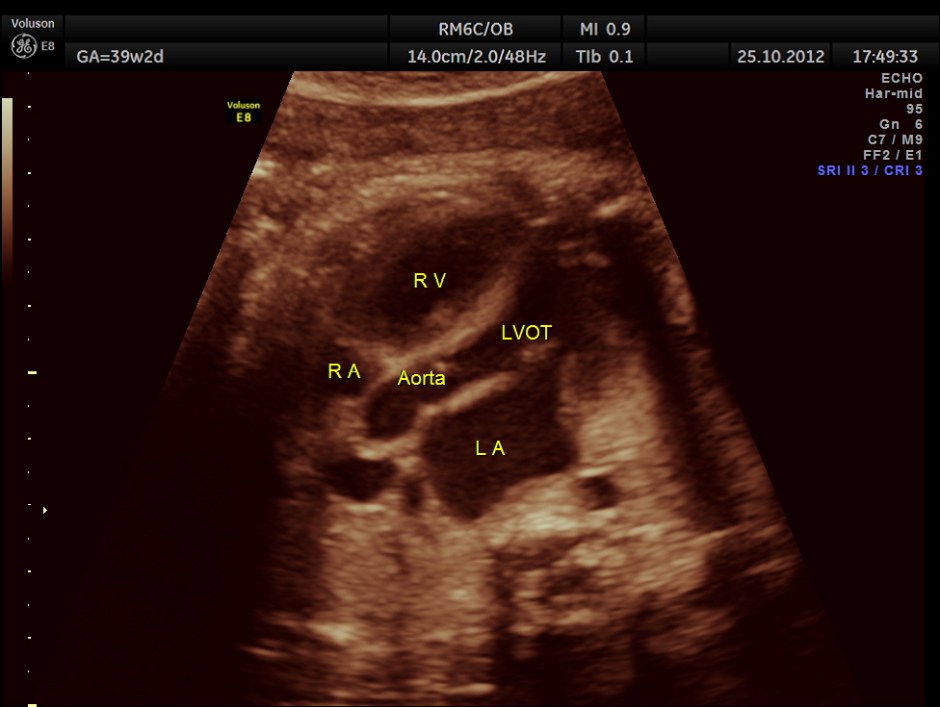

THIS FETUS HAD SEVERE FETAL ANEMIA WITH CARDIAC FAILURE LEADING TO CARDIOMEGALY WITH MITRAL, TRICUSPID AND PULMONARY REGURGITATION .NO OTHER OBVIOUS CARDIAC ANOMALY WAS MADE OUT . THE VENO ATRIAL , ATRIO VENTRICULAR AND VENTRICULO ARTERIAL CONCORDANCE APPEARED TO BE NORMAL; NO SEPTAL DEFECT WAS MADE OUT.